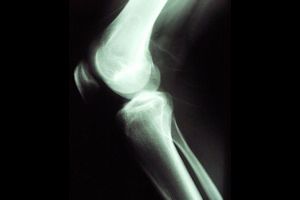

Cómo tratar el síndrome femoropatelarUn paciente padece el síndrome femoropatelar cuando la rodilla le duele porque el cartílago de la articulación entre la rótula y el fémur está inflamado. Se produce por una alteración anatómica de la tibia, que produce una fricción indebida sobre este cartílago.

Imagen cortesía de Wikipedia (www.wikipedia.com). Licencia CC BY SA.